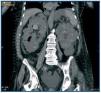

We report the case of a 76 year-old woman with hypertension, diabetes, chronic kidney disease secondary to polycystic hepatokidney disease in a peritoneal dialysis programme since March 2008, when she was admitted for fever, dysuria and haematuria. Laboratory tests showed elevated inflammatory parameters and the presence of E. coli from urine and blood culture tests. A CT scan showed a cyst on the upper right kidney complicated with air in the calices and bladder without prior manipulation of the urinary tract (Figure 1). Broad-spectrum antibiotic treatment with meropenem and gentamicin, according to the antibiogram sensitivity, was started and the patient was temporarily transferred to haemodialysis to treat intercurrent septic profile better. Despite this treatment, the patient continued to be febrile and showed a deterioration in her general condition. A new tomographic control was therefore done and a deterioration of the right kidney cyst was seen. Given the poor outcome of the septic profile with a lack of response to treatment, a right radical nephrectomy was performed, which revealed multiple kidney cysts filled with pus (Fig. 2). Further evolution was slow towards the improvement of her general condition, with a practical resolution of fever and progressive normalisation of the inflammatory parameters. Finally, the patient was able to be released after a long period of convalescence in a clinical and haemodynamically stable state, continuing kidney replacement therapy with regular haemodialysis.

Figure 1.